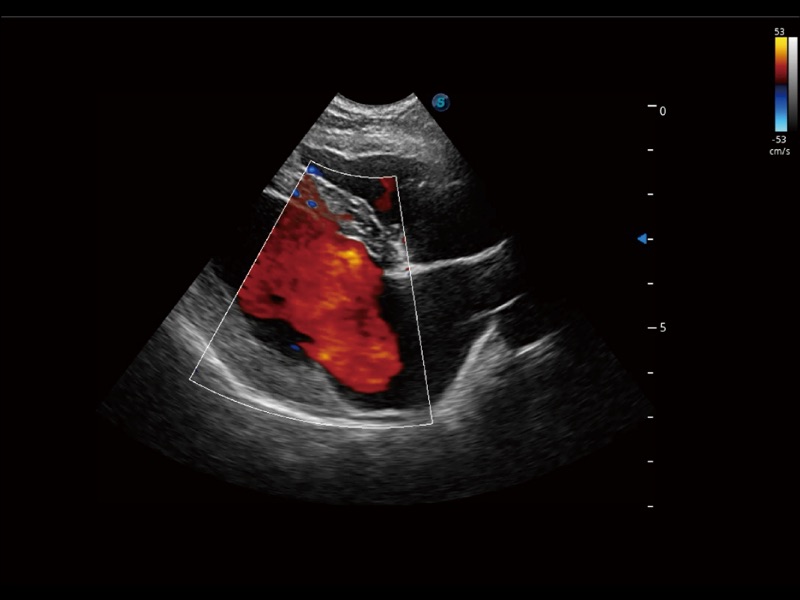

采用紅、橙、黃、綠、青、藍(lán)、紫這七種肉眼最為敏感的色彩,直觀地顯示組織內(nèi)血流灌注的時(shí)間先后信息,更精準(zhǔn)捕捉血流灌注走行細(xì)節(jié)。